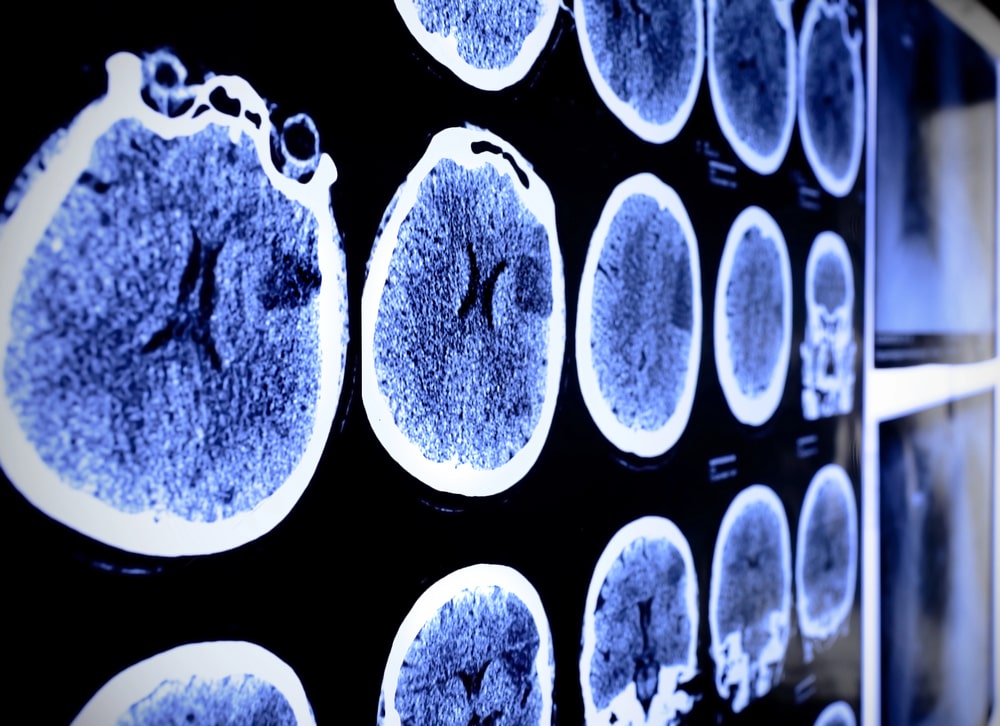

Diffuse axonal injuries, for example, occur when the brain’s nerve fibers are stretched or torn during impact. These injuries may not show up immediately on imaging scans but can still cause lasting neurological impairment. This delayed progression underscores the importance of early medical evaluation after any collision involving a head injury.